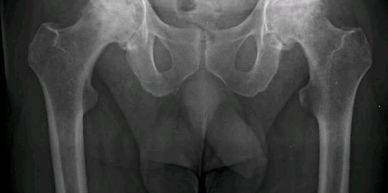

Paciente de 52 años, con artrosis bilateral de cadera. Se realizó una artroplastía total de cadera bilateral en un tiempo.